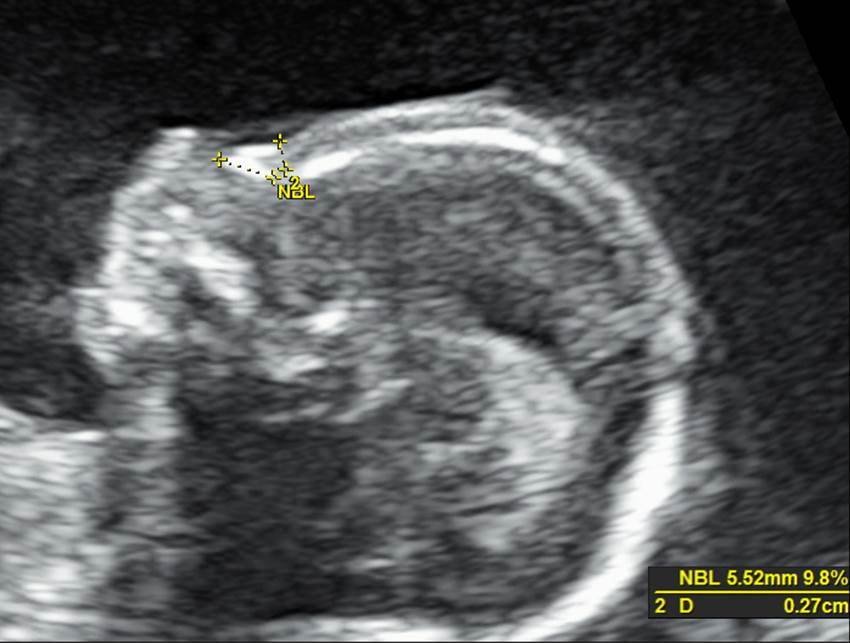

Вопрос 7

Оцените профиль плода в 20 недель